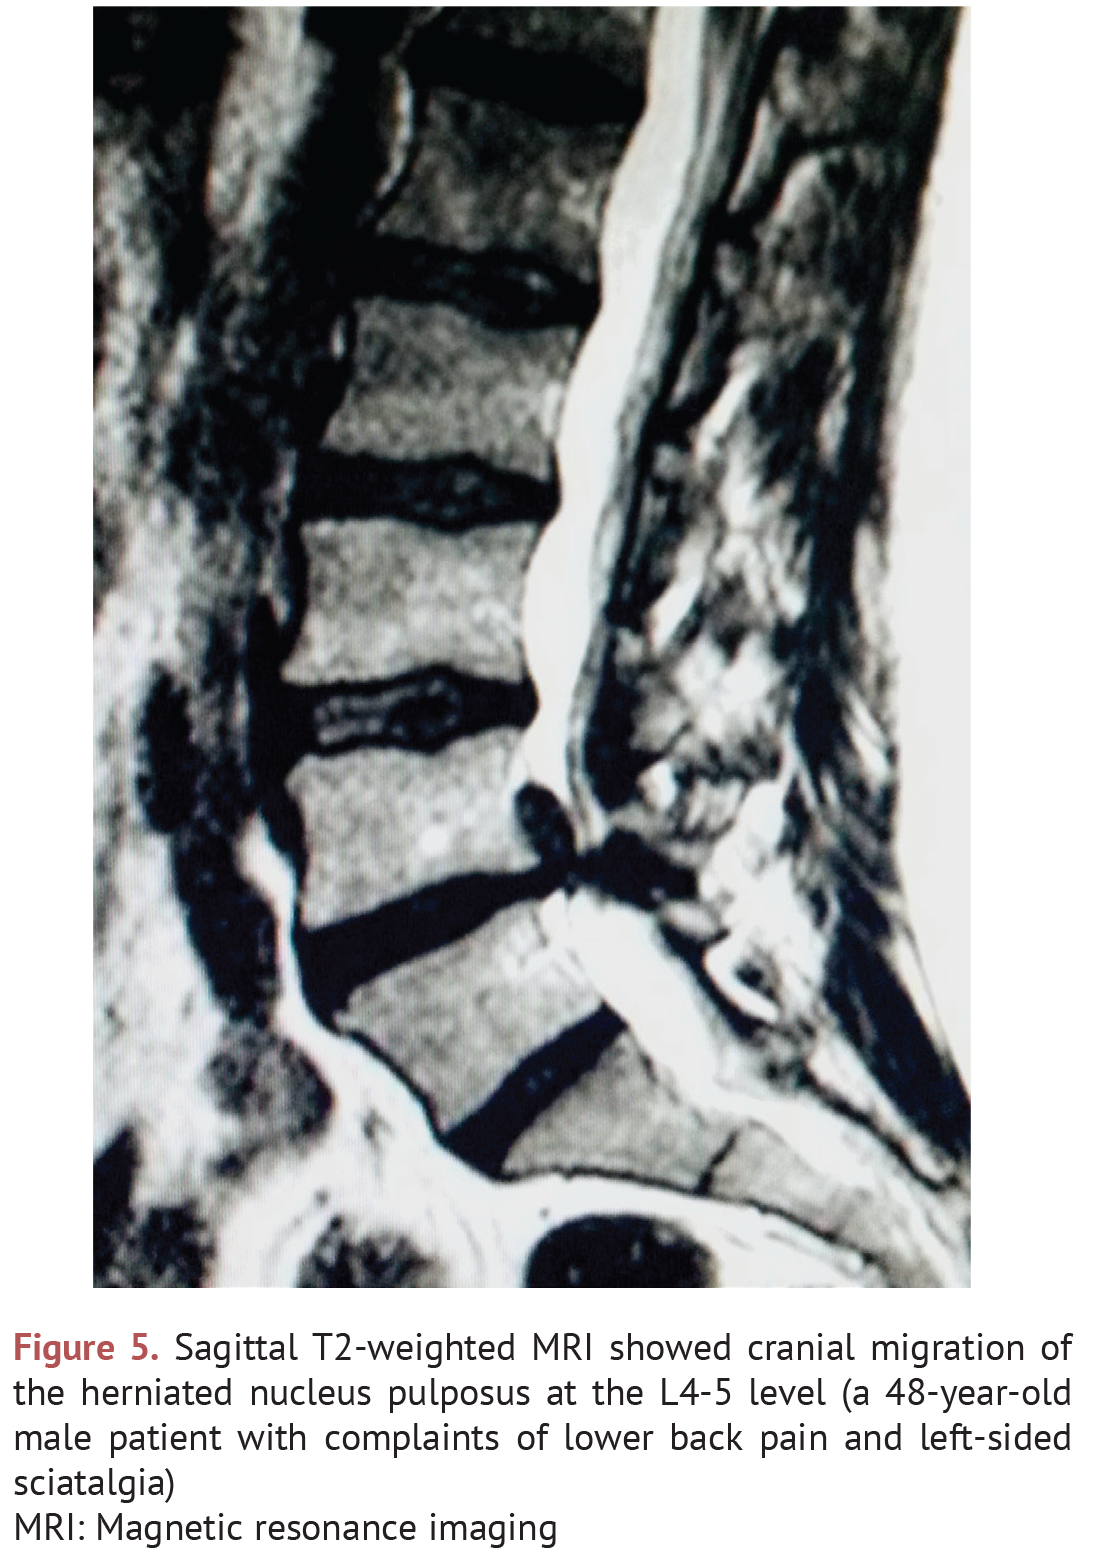

(PDF) Cranially migrated lumbar intervertebral disc herniations A Lumbar Herniation Journal Lumbar disc herniations are common causes of lower back and leg pain. Lumbar disc herniations are common causes of lower back pain, neurological dysfunction, and buttock/leg pain. In the absence of cauda equina syndrome, motor, or other serious neurologic deficits, conservative treatment should be the. Disc herniations can manifest in lumbar radiculopathy, neurogenic claudication, and cauda equina syndrome based on. Lumbar Herniation Journal.